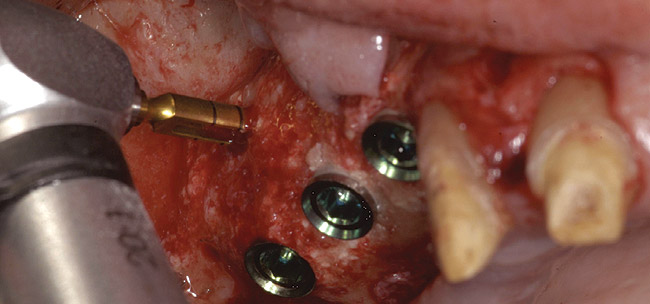

A 72-year-old man was referred for removal of failing maxillary right posterior implants (Figure 19). The treatment plan included removal of three implants with simultaneous bone augmentation and replacement implants for implant-supported fixed bridgework. Implant removal and bone grafting with rhPDGF (Gem 21®, Osteohealth, www.osteohealth.com) and allograft (MinerOss) and xenograft (BioOss®, Geistlick, www.geistlickonline.com) were used along with titanium mesh for space maintenance (Figure 20, Figure 21 and Figure 22). Six months later, mesh removal revealed type I bone allowing for placement of three implants (Figure 23 and Figure 24).

Figure 22  Titanium mesh fixation.

Figure 22

Figure 23  Trephinated core biopsy obtained at 5 months.

Figure 23